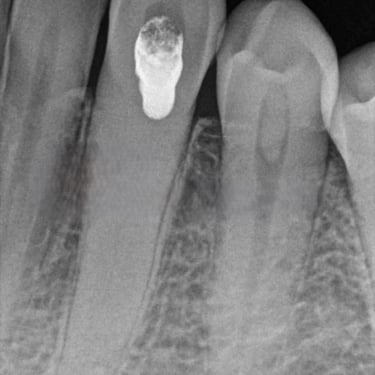

Calcificación Pulpar

La calcificación pulpar es la formación de depósitos de calcio dentro de la pulpa dental, que puede dificultar el tratamiento de conducto.

Los pacientes generalmente no tienen síntomas, pero pueden experimentar sensibilidad.

El tratamiento incluye la eliminación de los depósitos durante el tratamiento de conducto. Es importante tratarlo para evitar complicaciones durante el procedimiento.